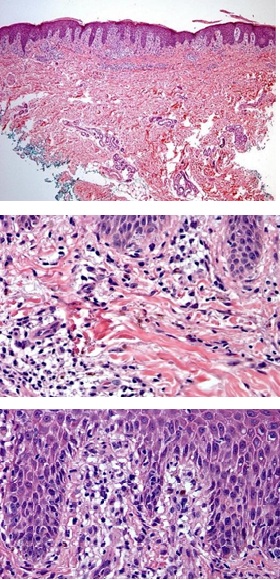

A biopsy of the helix was performed that returned inconclusive, so a second sample was taken from the anterior surface of the right forearm, which reported epidermis covered by basket-weave orthokeratosis with isolated patches of parakeratosis, irregular elongation of the rete ridges, multiple foci of spongiosis and extensive vacuolar damage to the interface with pigmentary incontinence (Figures 3 & 4). Also, on the dermis, moderate superficial and interstitial perivascular inflammatory infiltrate composed of lymphocytes, histiocytes and occasional eosinophils and dilated capillaries (Figure 5). These histological findings are compatible with a cutaneous reaction to drugs, probably due to emtricitabine, so a change to medication was suggested.

Figures 3,4 and 5: Histology images.